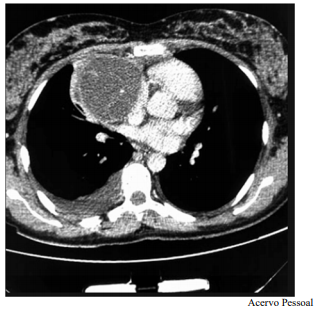

Um paciente de 17 anos de idade revela idas frequentes à emergência por causa de tosse e dispneia. Em exame de imagem investigatório, identificou-se, na tomografia computadorizada de tórax (TCT), uma massa mediastinal anterior bem definida, com densidade de partes moles, medindo cerca de 17 cm x 11 cm x 10 cm, conforme representado na imagem a seguir. A lesão não invadia estruturas adjacentes, e não foram encontradas outras alterações nas tomografias de tórax, de crânio e de abdome. Foi realizada uma biópsia pré-operatória guiada por TCT, cujo diagnóstico foi compatível com teratoma de mediastino.

Considerando esse caso clínico, a imagem apresentada e os conhecimentos médicos correlatos, julgue o item a seguir.

O quadro clínico apresenta um tumor de mediastino anterior. O teratoma cístico maduro trata-se da neoplasia mais comum das células germinativas do mediastino.